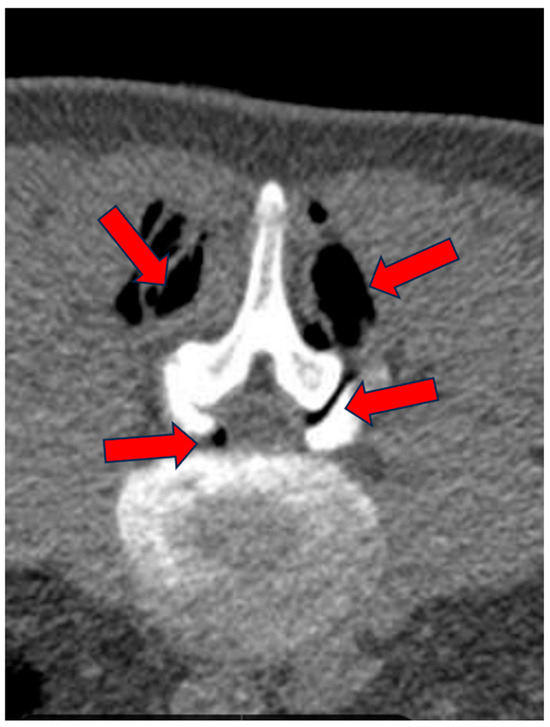

A medical record was created for each patient at enrollment, which collected key information such as age, date of birth, date of enrollment, date of treatment, and clinical details regarding the type of pain, radiation of pain, presence of paresthesias, Lasègue sign, sensitivity levels, lower limb reflexes, and plantar and dorsal extensions of the foot, as well as dorsal extension of the great toe. The study included patients suffering from advanced degenerative zygapophyseal osteoarthritis, lumbar disc disease (including multilevel), segmental canal stenosis, and pseudospondylolisthesis, with evidence from CT or MRI (Figure 1, Figure 2 and Figure 3).

Figure 3.

(A–D): FG of 77-year-old male treated at L4–L5 and L5–S1 levels. (A,B) Sagittal CT reconstructions using algorithms for both parenchyma and bone. L4–L5 spondylolisthesis (arrows), degenerated and thinned L5–S1 disc with vacuolated left paramedian herniation (arrow). (C) Axial CT scan at L4–L5: bilateral paramedian central protrusion of the annulus (arrows). (D) Axial scan at L5–S1: partially vacuolated left paramedian herniation causing indentation on the emergence of the left S1 nerve root (arrow).